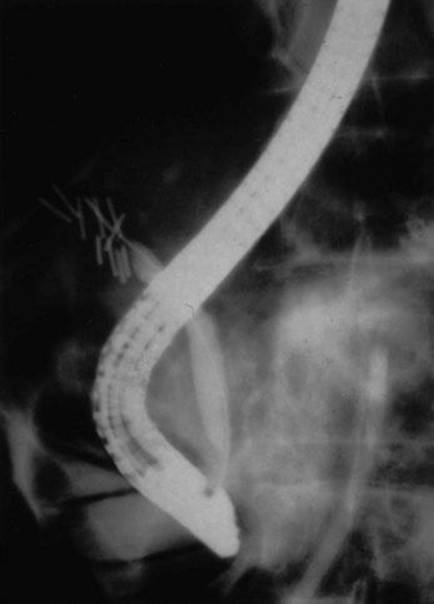

4 In this intraoperative cholangiogram, the arrow points to what duct?

image

Comments

Variations in the anatomy of the extrahepatic bile ducts occur commonly. The surgeon must be cognizant of these variations and learn to recognize and identify them to prevent inadvertent injury to the bile ducts during cholecystectomy. Approximately two thirds of individuals have the “textbook” anatomy, with the anterior (segments V and VIII) and posterior (segments VI and VII) sectional ducts from the right joining to form the main right hepatic duct, which then joins the main left hepatic duct to form the common hepatic duct. In 15% to 25% of individuals, the anterior or posterior sectional duct from the right lobe inserts separately into the common hepatic duct. When the posterior duct inserts separately, it is usually at a greater distance caudally from the junction of the left duct and the other right duct than when the anterior duct inserts separately. This duct is therefore at risk for injury during cholecystectomy if the anatomy is not recognized.

One of the most common variations in cystic duct anatomy is direct insertion into one of these separately inserting right hepatic ducts, as the pictured cholangiogram demonstrates. The terms “crossover duct” and “accessory duct” are misnomers for this arrangement. True accessory ducts are rare and occur when there is embryologic duplication of the bud that forms the bile ducts and liver.